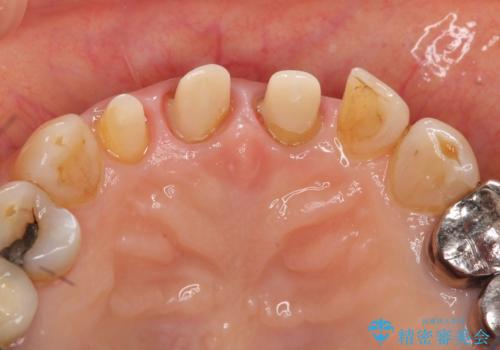

前歯の審美改善

- 孫娘の結婚式に合わせて前歯を綺麗にして写真映りをよくしたいと来院されました。

結婚式に合わせて根管治療からのやりかえを短期集中治療で計4回で終える計画を立てます。

- 40万円(仮歯・ファイバーコア・ジルコニアクラウン×3)費用は治療当時の料金となります